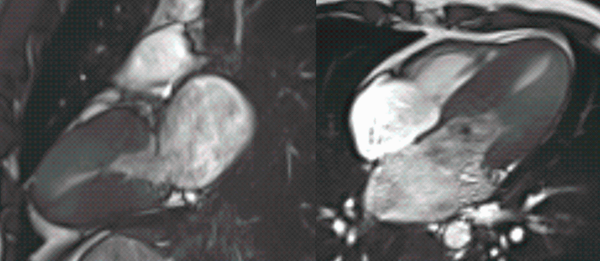

This 57-years old presented with acute chest pain. She was diagnosed to have a non-STEMI infarct. Coronary angiography and echo were done. Based on the echo findings, an MRI was done, which uncovered a myriad of findings.